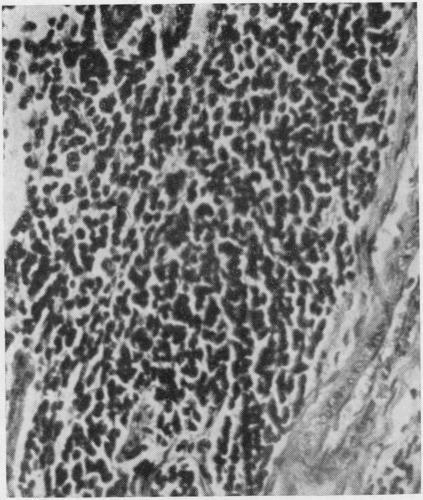

先天性神经母细胞瘤

CONGENITAL NEUROBLASTOMA.

Abstract

The clinical histories and post-mortem findings in five cases of neuroblastoma are described, and an account given of the microscopic characteristics of the tumours. In four of the cases the tumour was present at birth and was probably so in the fifth case. In only one case was the presence of the malignant tumour a significant factor in causing death. The differential diagnosis of such tumours is discussed.The accumulated evidence of many recorded cases suggests that neuroblastoma, becoming manifest in the early months or weeks of life, and congenital tumour, would be included in such a group, and has an appreciably better prognosis than has this same tumour when it becomes manifest in later childhood. The literature is briefly reviewed to illustrate this aspect of prognosis and possible reasons for it are indicated.

摘要

本文描述了5例神经母细胞瘤的临床病史和尸检结果,并阐述了肿瘤的微观特征。其中4例肿瘤在出生时就已存在,第5例可能也是如此。只有1例中,恶性肿瘤的存在是导致死亡的重要因素。文中讨论了此类肿瘤的鉴别诊断。许多已记录病例的累积证据表明,在生命最初几个月或几周内出现症状的神经母细胞瘤以及先天性肿瘤,应归为同一组,其预后明显优于在儿童后期出现症状的同类型肿瘤。本文简要回顾了相关文献以说明预后的这一方面,并指出了可能的原因。